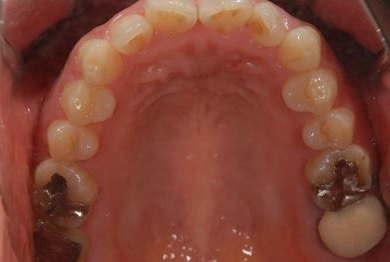

インプラント治療+セラミック治療+歯肉歯槽骨整形

| 性別/年齢 | 女性 / 38歳 | ||||||||||||||||||||||||||||||||

| 主訴 | 右下奥の欠損のため、インプラントを希望。また、左に物が挟まりやすいための治療も希望。 | ||||||||||||||||||||||||||||||||

| 治療方針 | 欠損部分を、インプラント治療にて、機能的・審美的回復を行う。 | ||||||||||||||||||||||||||||||||

| 治療内容 | インプラント1本、ジルコニアフレームオールセラミッククラウン2本(ジルコニアセラミック用土台1本)、歯肉歯槽骨整形 | ||||||||||||||||||||||||||||||||

| 総治療費 | 713,580円 | ||||||||||||||||||||||||||||||||

| 治療期間 | 10ヶ月 |